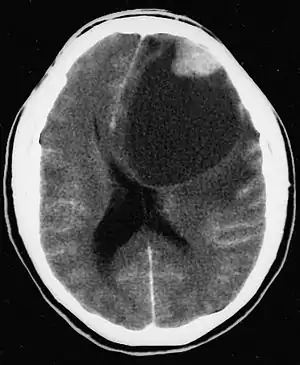

| CT scan of a brain with pleomorphic xanthoastrocytoma. The classic radiographic appearance is one of a superficially situated tumor, here a mural nodule, associated with an underlying cyst. | |